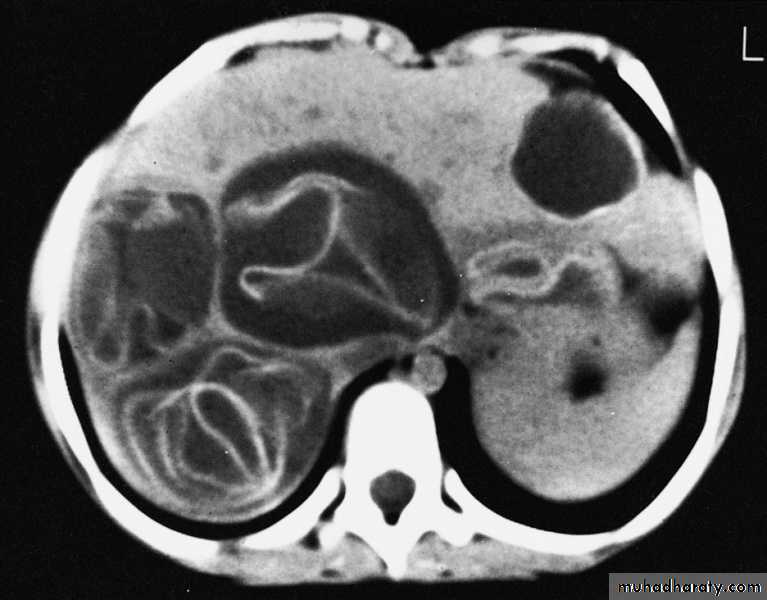

Hemangioma